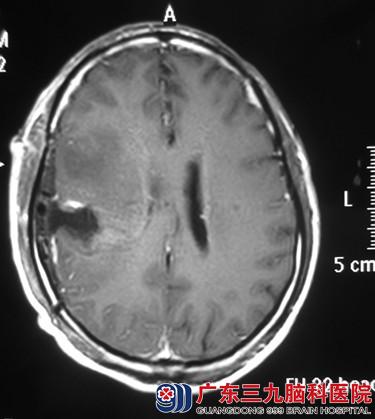

经头颅MR检查提示右额叶占位,直径约3cm。完善相关检查后,由鲁明主任主刀,术前导航计划,显微镜下见肿瘤呈灰白色,血供丰富,术中再次导航定位肿瘤位置,电生理监测避开脑功能区,唤醒患者,在患者语言及肢体运动配合下,连同受侵犯脑皮层一并全切肿瘤,手术顺利结束。术后经过专科治疗护理,王先生语言、肢体活动正常,未出现功能障碍。术后病理结果:胶质瘤(WHO IV级)。

术后